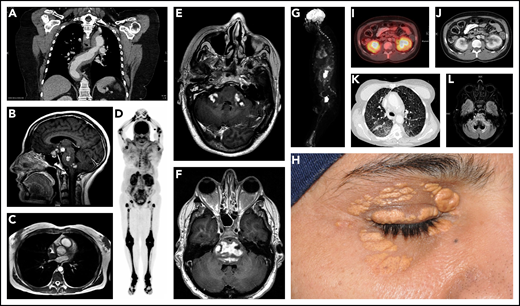

Diverse manifestations of ECD. (A) Coronal postcontrast chest computed tomography (CT) demonstrates extensive soft tissue sheathing of the thoracic aorta. (B) Enhancing lesions in the hypothalamic pituitary axis (HPA), brainstem, and cerebellar peduncle is shown in sagittal gadolinium enhanced T1 magnetic resonance imaging (MRI). (C) Three-dimensional fast imaging using steady-state acquisition (3D-FIESTA) MRI of the heart showing right atrial mass from ECD. (D) Maximal intensity projection (MIP) of 18F-fluoro-deoxyglucose (FDG)–positron emission tomography (PET) demonstrates typical hypermetabolic ECD lesions throughout the appendicular skeleton with greatest activity of the disease in the legs. (E) Irregular bilateral enhancing of ECD lesions in the middle cerebellar peduncles are demonstrated by postgadolinium axial T1 MRI. (F) Expansile irregularly enhancing ECD lesions in the pons seen on postgadolinium axial T1 MRI. (G) MIP of FDG-PET demonstrating ECD lesions with increased uptake in distal femur, orbit, multilevel thoracolumbar spine roots, and right atrium. (H) Periorbital xanthelasmas from ECD. (I-J) “Hairy kidney” hypermetabolic and contrast-enhancing perinephric infiltrates are shown on axial-fused FDG PET-CT and contrast-enhanced axial CT scan. (K) High-resolution axial CT scan image of the chest demonstrating reticulonodular opacities from ECD. (L) Atrophic or neurodegenerative changes in the brainstem and cerebellum are shown by axial T2-FLAIR MRI.